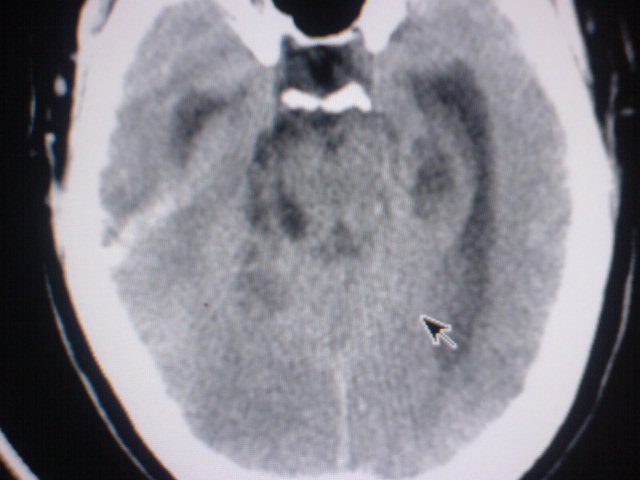

标题: CT17158:抽搐 [打印本页]

标题: CT17158:抽搐

脑积水,原因待查。

资料太少,大胆推测:脑干病变,中央孔受阻致脑脊液回流障碍脑积水。

考虑1小脑吲占位,2四脑室室管膜瘤

中线松果体区肿瘤?做增强会有帮助鉴别